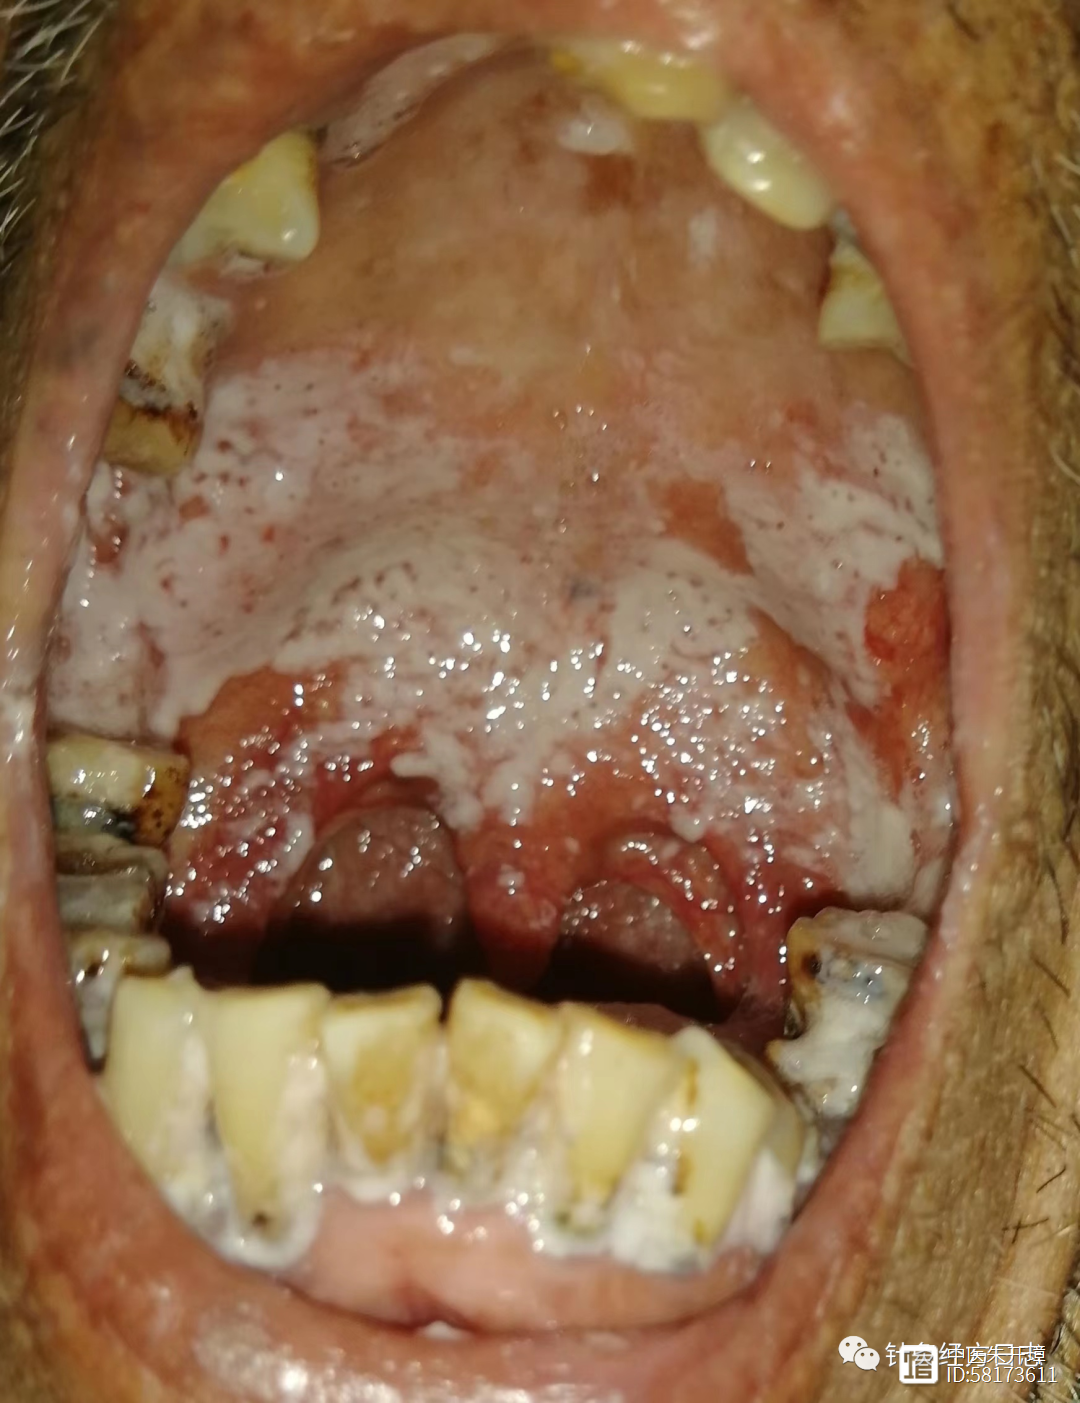

牙洞疼多久神经会死掉(忍一时疼得要命 扛一扛钱包花空)

特别能吃苦,特别能忍耐一直被认为是中国人的传统美德,可是在生病这一项上,忍耐跟美德一毛钱关系也没有。牙病更是如此,忍来忍去,最后总会爆发在你最不想发生的时间里,比如过年。在刚刚过去的春节里,大家压抑了三年的情绪终于得...